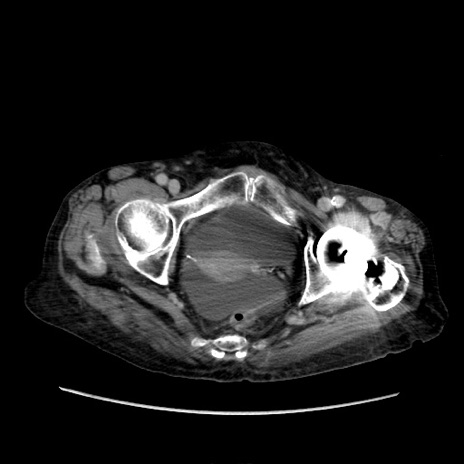

症例31(横断像)

【症例】80歳代 女性

【主訴】腹部膨満感

【現病歴】他院にて肝硬変にてフォロー中。1週間前から便秘、腹部膨満感、臍部腫瘤あり受診となる。

【既往歴】肝硬変

【身体所見】腹部膨隆あり、皮膚変化なし、疼痛なし。

【データ】WBC 4600、CRP 0.25